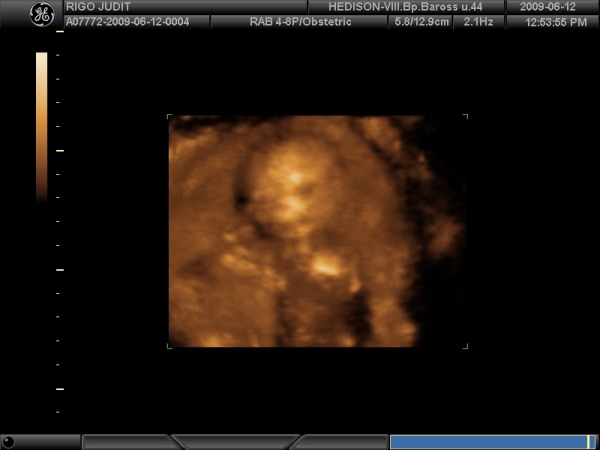

A védőnőnél ma együtt voltunk az új barinővel, kocsival vitt fel, ezért kivi is voltam a vérnyomira így hogy nem rohanásban volam és dombmászásban. Most 124/94 volt, de a pulzusom meg valamiért 122. Hát már nem tudom mi a fene van. Remélem nem kapok majd gyogyit, és csak a meleg miatt van.

A holnapi dokit már baromira várom.

Lehet hogy ezért alszom mostanában olyan rosszul, mert türelmetlen vagyok hogy rég láttam őkelmét, és szeretném már tudni hogy jól van minden oké van odabent.